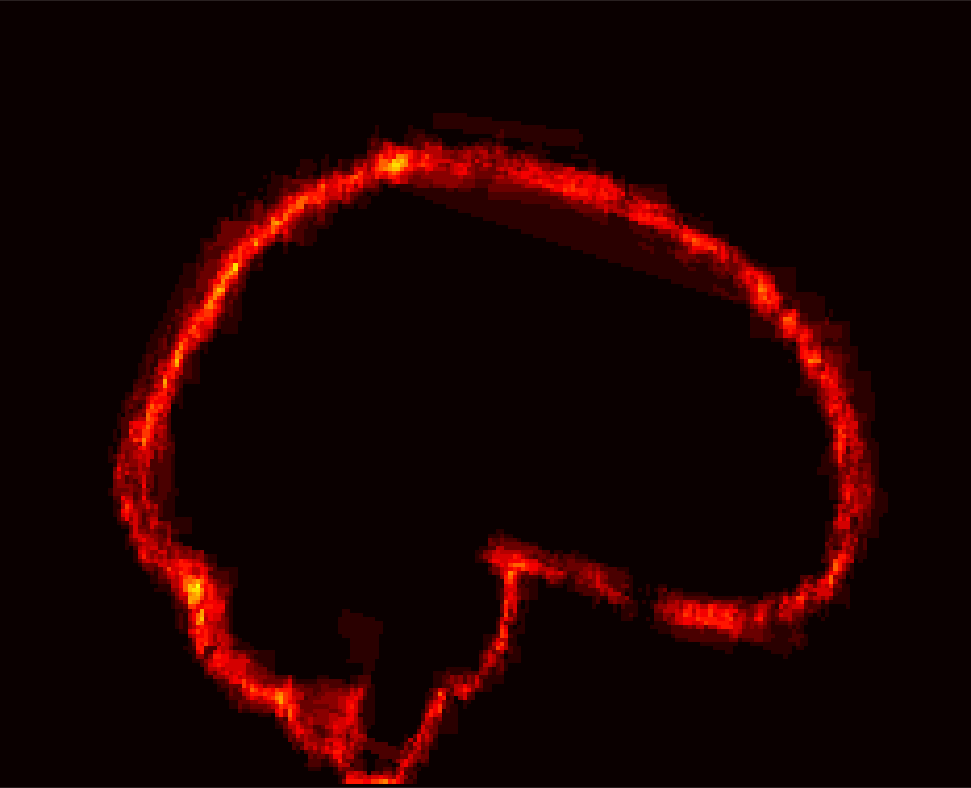

[Uncaptioned image] [Uncaptioned image] [Uncaptioned image] [Uncaptioned image]

(a) (b) (c) (d)

Figure 8: Example BRATS image with its decomposition result in atlas space. (a) Input image after pre-processing; (b) quasi-normal image L+M𝐿𝑀L+M; (c) non-brain image S𝑆S; (d) pathology image T𝑇T.

In addition to extracting the brain from pathological datasets, our method also allows for the estimation of a corresponding quasi-normal image in atlas space, although this is not the main goal of this paper. Fig.8 shows an example of the reconstructed quasi-normal image (L𝐿L) for an image of the BRATS dataset, as well as an estimation of the pathology (pathology image T𝑇T and non-brain image S𝑆S). Compared to the original image, the pathology shown in the quasi-normal image has been greatly reduced. Hence this image can be used for the registration with a normal image or a normal atlas. This has been shown to improve registration accuracy for the registration of pathological images [27]. Furthermore, an estimate of the pathology (here a tumor) is also obtained which may be useful for further analysis. Note that in this example image the total variation term captures more than just the tumor. This may be due to inconsistencies in the image appearance between the normal images (obtained from OASIS data) and the test dataset. As our goal is atlas alignment rather than quasi-normal image reconstruction or pathology segmentation, such a decomposition is acceptable, although we could improve this by tuning the parameters or applying regularization steps as in [27].